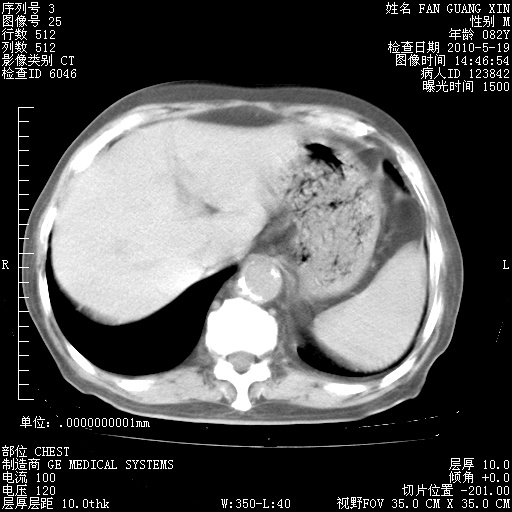

治疗3周后的肺部CT纵隔窗

从胸部影像学来看,的确有好转。至于目前为何发热不甚清楚?除了发热还有其他症状如有无喀痰,痰呈丝状吗?等等。尽量搜寻有无致发热其它可能原因?真菌?其它?如果的确无其他致发热的原因,考虑将甲强龙调至60-80mg bid/日。免疫全套基本无异常,考虑多系特发性肺间质纤维化